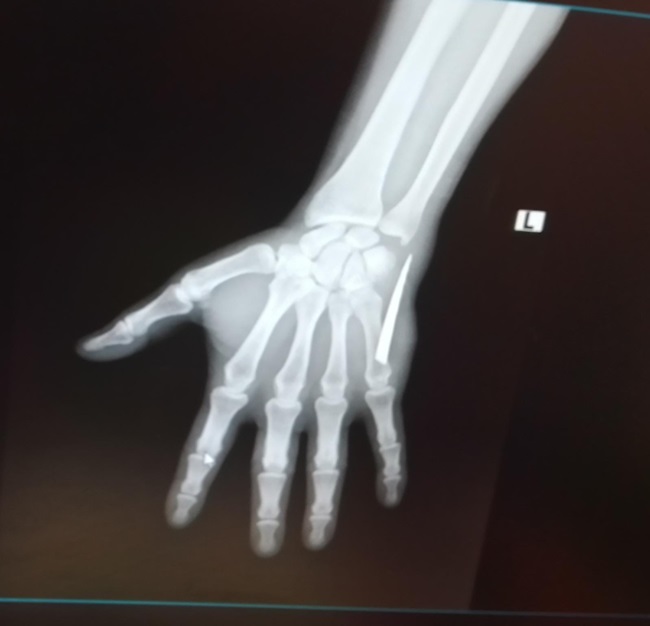

Zonguldak’ta iki ay önce eline girdiğinden haberi olmadığı bıçak parçasıyla 2 ay boyunca yaşayan tır şoförü Doğukan Köseli, çektirdiği röntgen filminde hayatının şokunu yaşadı. Acısını dindirmek için mücadele veren genç adam, iddialara göre kendisine bu acıyı yaşatanlara karşı hukuk mücadelesi başlatacak.

2 Ekim Pazar günü öğleden sonra evinin mutfağında oturduğu esnada ayağa kalkmaya çalışan Doğukan Köseli, dengesini kaybedip yere düştü. O sırada elinde olan meyve bıçağı kırılarak parçası genç adamın eline girdi. Durumdan habersiz olan Köseli, saat 16.00 sıralarında Devrek Devlet Hastanesi aciline giderek tedavi olmak istedi. İddialara göre röntgen çekilmeden eline yapılan zımba dikişi sonrası 5 santimetrelik bıçak parçasıyla yaşamaya başlayan Köşeli enfeksiyondan kaynaklandığı belirtilerek, başka bir sıkıntı olmadığı gerekçesi ile tekrar evine gönderildi. Genç adam yaşadığı acı dolu günleri İHA’ya anlattı.

İki aydır eliyle bilek arasında kırılan bıçak parçasıyla yaşadığından habersiz olan Doğukan Köseli, “Tır şoförüyüm. Geçirdiğim kaza yüzünden belimde sıkıntım vardı. Mutfakta kalkmak isterken bıçağın üzerine düştüm. O esnada bıçak kırıldı ama parçasını göremedim. Eşimle beraber elimi sarıp Devrek Devlet Hastanesi aciline gittik. Pansuman yapacağız diye yarım saat beklettiler donra doktor Ekrem Sönmez herhangi röntgen işlem falan yapmadan elime bakıp zımba atılmasını söyledi. Kan kaybettiğim için kimse dokunamadı. Doktor Ekrem bey kendisi zımba attı. Sonrasında elimi sardılar, beni eve gönderdiler. Aradan geçen zaman zarfında dikiş yerlerim iyileşmeye başladı fakat bir yerinde yara oluştu. Sürekli kanama yapmaya başladı. Bu sebepten ötürü birkaç defa hastaneye gittiğimde pansuman yapıp gönderdiler. Film çekilmesini istedim, ‘Kırık, çıkık için film çekilir bu kadar yara için film çekilmez’ dediler. 28 Kasım Pazartesi günü daha şiddetli bir ağrıyla uyandım. Elime baktığımda bir parça olduğunu hissettim. Küçük bir parça sandım eşimle almaya çalıştık ama baya büyük olduğunu fark ettik. Bunun üzerine Çaycuma Devlet Hastanesi’ne geldik. Hemen röntgen çekildi ve elimdeki parçanın baya büyük olduğu söylenildi. Sonrasında ameliyat ile bıçağın parçasını aldılar."

5 santimetrelik bıçak parçasının yaşattığı acı nedeniyle elini kullanamadığını ve dolayısıyla da iki ay boyunca çalışamadığını söyleyen Köseli, "Parmakta uyuşma, ağrı yapıyordu. Koluma engel olmaya başlamıştı. Güç kaybı da yaşayınca işsiz kaldım. Elimdeki bıçak parçası yüzünden hem elimden oluyordum hem de işsiz kaldım. Elim sürekli sargı içindeydi ve sürekli kanama yaşıyordum. Sargıyı çıkardığım zaman kanamam aşırı derecede artıyordu. Kan kaybı yüzünden kan oranlarımda da düşüklük çıktı. Kanama olmasına rağmen iyice temizlemeye çalıştım. O esnada elimin içinde bir şey olduğunu fark ettim. Elimle dışarıdan doğru ittirmeye başladım. Yüzeye doğru parça geldi. Korkutan gerçek, Çaycuma Devlet Hastanesi’ne gelince meydana çıktı. Çıkan parçada gördünüz gibi büyük ve tırtıklı bir bıçak. Tırtıklı bıçak normal bıçak yüzüne göre daha zararlı. Kolumda da baya hasar oluşturdu” dedi.